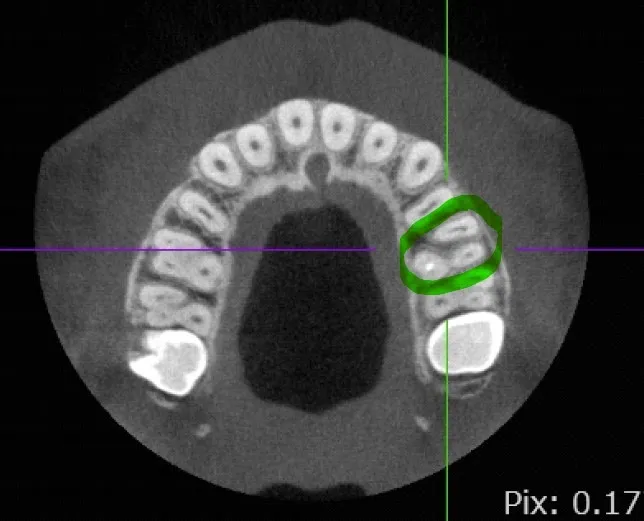

こちらは最初のレントゲン写真をとらせてもらった方のCT写真の断面図になります。

CT写真は最初のレントゲンと違い、三次元的に骨や歯を見ることができます。

画像内で緑で覆ってるものが左上6番目の歯になるのですが、前の方に位置してる根が横に広いものであることが分かります。

目視上では4つ根があるように見えても、実際はそのうち2つの根が融合しており、それゆえ大きい根管になっておりました。ややこしい。